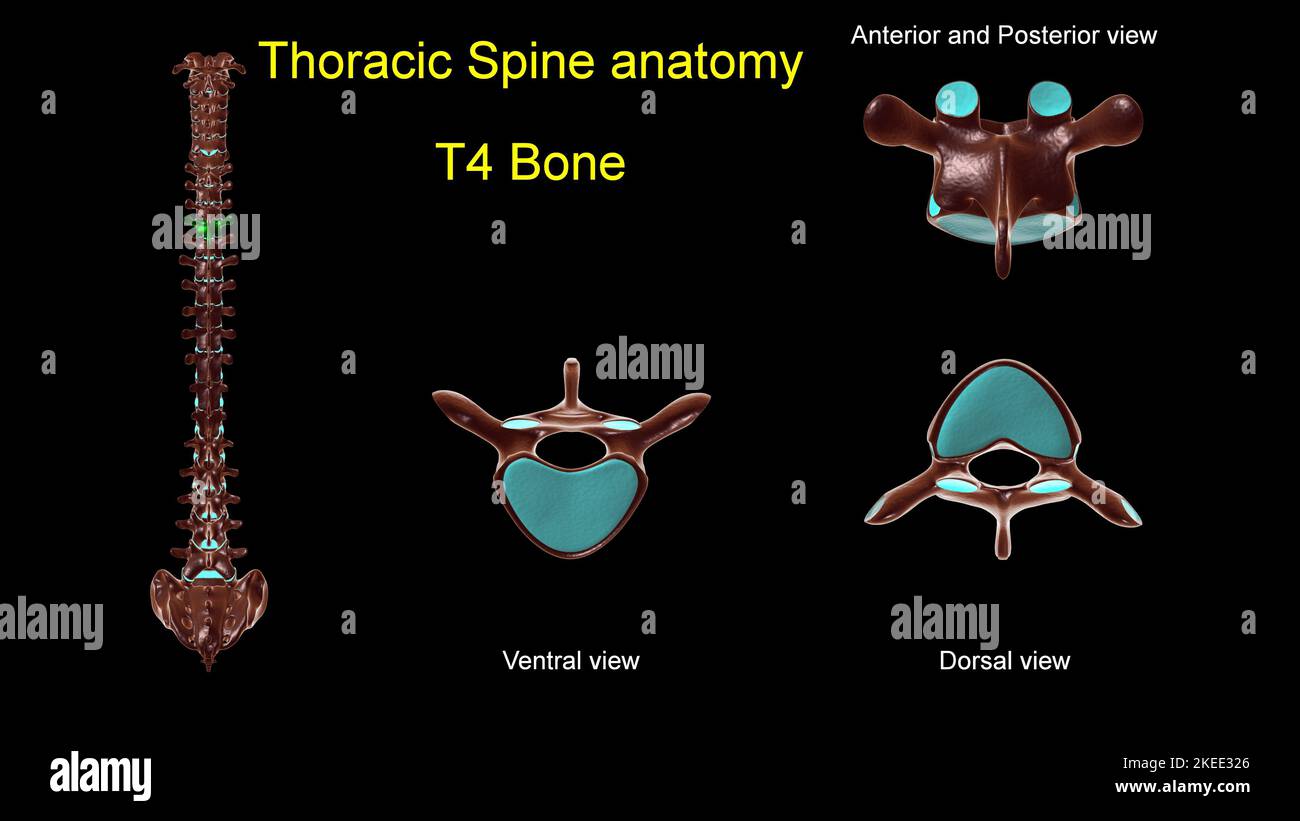

RF2KEE32B–Colonna toracica T 1 anatomia ossea per concetto medico 3D Illustrazione con vista anteriore e posteriore

RF2KEE329–Colonna toracica T 11 anatomia ossea per concetto medico 3D Illustrazione con vista anteriore e posteriore

RF2KEE342–Colonna toracica T 3 anatomia ossea per concetto medico 3D Illustrazione con vista anteriore e posteriore

RF2KEE326–Colonna toracica T 4 anatomia ossea per concetto medico 3D Illustrazione con vista anteriore e posteriore

RF2KEE34K–Colonna toracica T 7 anatomia ossea per concetto medico 3D Illustrazione con vista anteriore e posteriore

RF2KEE333–Colonna toracica T 6 anatomia ossea per concetto medico 3D Illustrazione con vista anteriore e posteriore